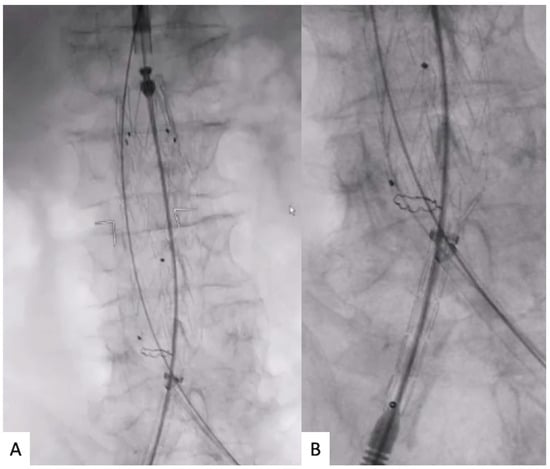

Then, the Dryseal introducer was lowered just below the markers of the contralateral gate; an aortography was performed from the placed 5 Fr pigtail, to visualize the renal arteries; and the stent-graft main body was deployed in a crossed limb “ballerina” or standard configuration depending on the previous orientation. Such steps aim to obtain a supported sheath as close as possible to the contralateral gate opening, to speed up the CGC (Figure 3A). A standard J-tip guidewire is inserted into the 5 Fr pigtail to lower it just below the opening of the contralateral gate at the same level as the 16 Fr Dryseal introducer tip. The CGC begins using the same 5 Fr pigtail and the standard J-tip guidewire; both the J-tip guidewire and 5 Fr pigtail can be exchanged to facilitate CGC (Figure 3B).

Figure 3.

(A) Contralateral supported sheath lowering below the contralateral gate radiopaque markers and main body deployment in ballerina configuration. (B) Contralateral gate cannulation with buddy wire through the contralateral supported sheath.